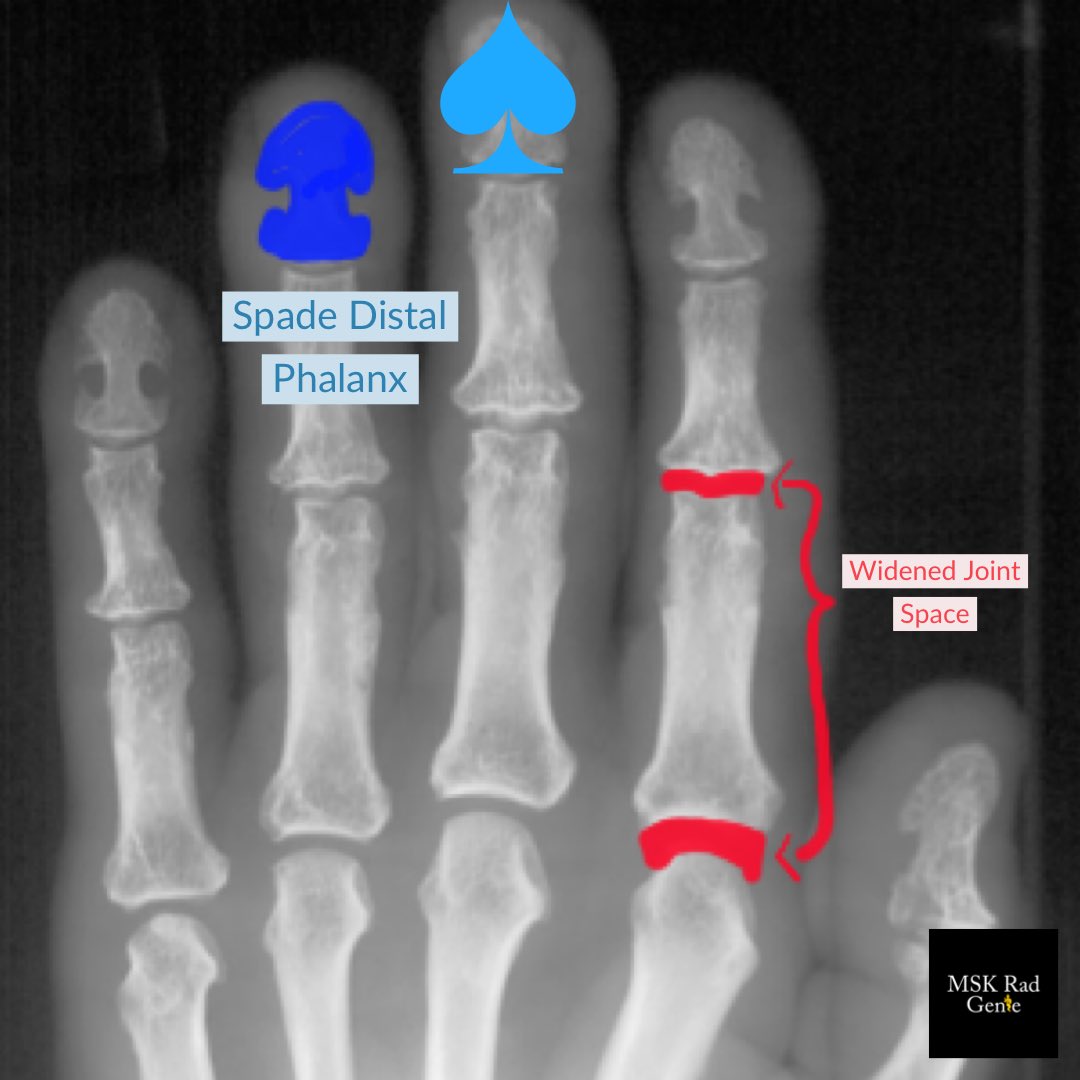

Typical MSK imaging findings in Acromegaly: 1. “Spade” hand distal phalanges 2. Frontal bossing 3. Enlarged sinuses 4. Widened joint spaces 5. Thickened heel fat pad (>2.5cm)

#RadRes#MSKRadpic.twitter.com/R3uLKomBnb